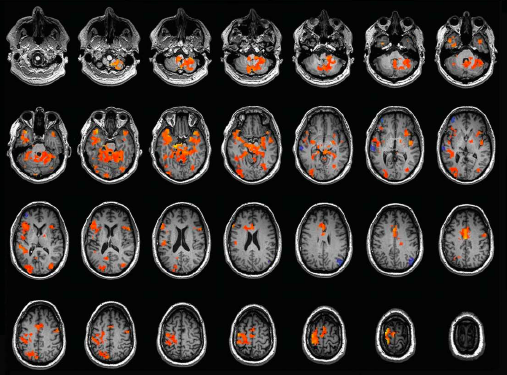

Un cas rarissime de #synesthesie émotionnelle après un AVC

#synesthesie #cerveau #neurosciences #neurologie